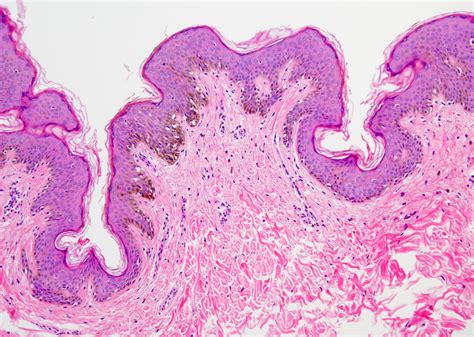

An Intradermal Pigmented Nevus is a type of mole that develops within the dermis, the layer of skin beneath the epidermis. Unlike other types of moles, which can be raised or flat, intradermal nevi are typically raised and have a smooth, dome-shaped appearance. They are often flesh-colored or slightly darker and can appear anywhere on the body. These nevi are usually present at birth or develop during childhood and adolescence.

• Dermoscopy: This non-invasive technique uses a specialized microscope to examine the mole more closely. It can help differentiate between benign and malignant lesions.

• Biopsy: In some cases, a biopsy may be performed to confirm the diagnosis. This involves removing a small sample of the mole for laboratory analysis.